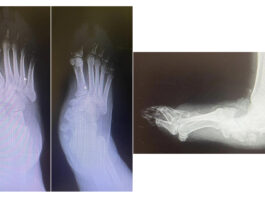

Piede piatto: efficacia dei plantari antipronazione

Il piede piatto è tra le più comuni alterazioni del piede. Nel tempo, questa condizione può contribuire a sviluppare problematiche alla spina...